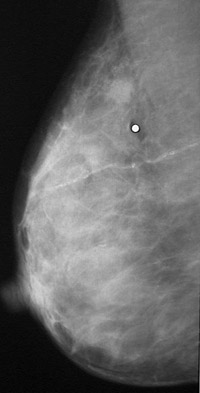

Click on the breast lesion in the mammogram above:

This mammogram demonstrates a lesion consistent with a neoplasm in the upper portion above and just to the left of the white dot marking the point the patient felt some pain on palpation. On biopsy, this was an infiltrating ductal carcinoma.